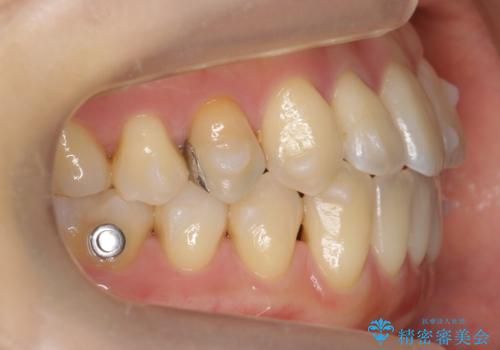

部分矯正コースでしたので左下67の段差は特に治しておりません。

右下567及び左下6の虫歯治療も一緒に行っています。